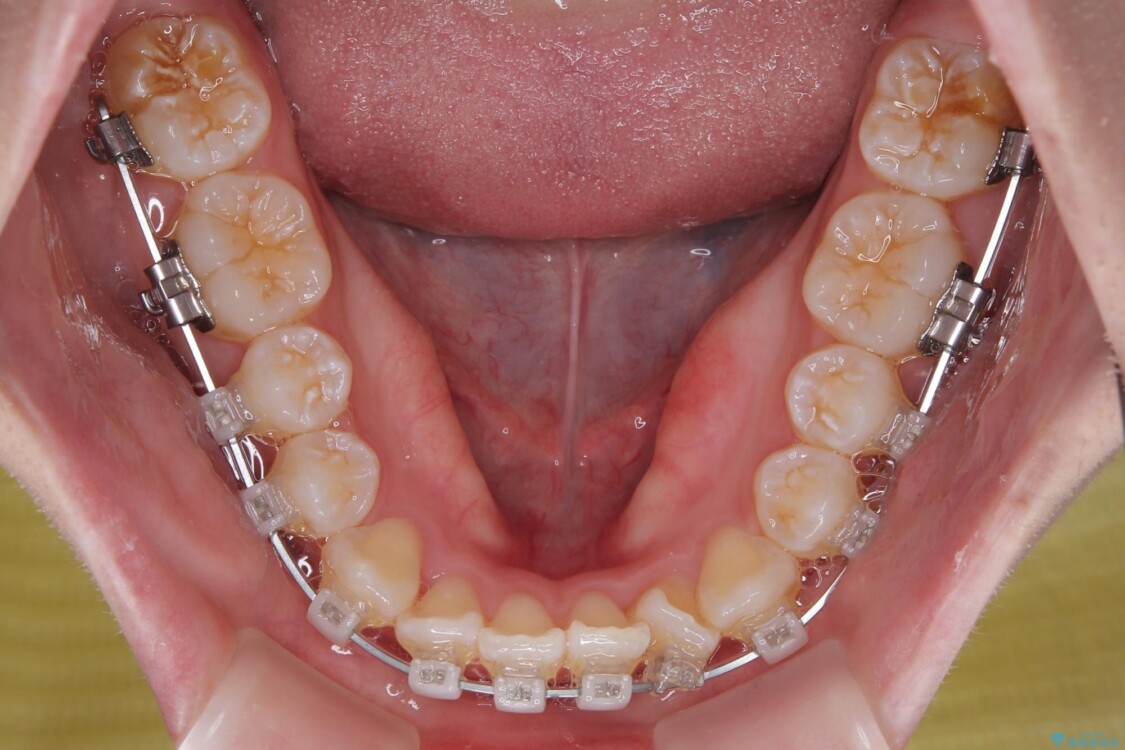

目立ちにくさと費用のバランスを考慮し、プラスチックブラケット+メタルワイヤーを採用。日常生活でも装置の存在感を気にせずお過ごしいただけます。

治療途中

• 【モニター】前歯のデコボコをスッキリ解消!目立ちにくいワイヤー矯正でスピーディに治療完了 治療途中画像